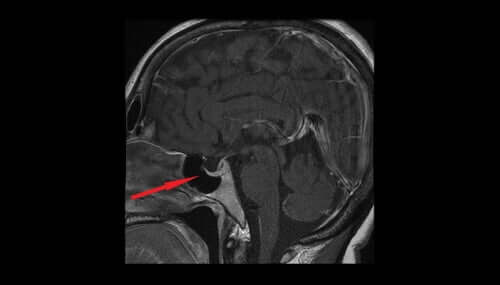

La vasopressine, également connue comme l’hormone antidiurétique ou ADH, est sécrétée par les noyaux magnocellulaires de l’hypothalamus. Elle passe ensuite dans la neurohypophyse et finalement dans le sang. Cette hormone aide à réguler la quantité d’eau dans l’organisme en contrôlant la quantité d’eau excrétée par les reins.